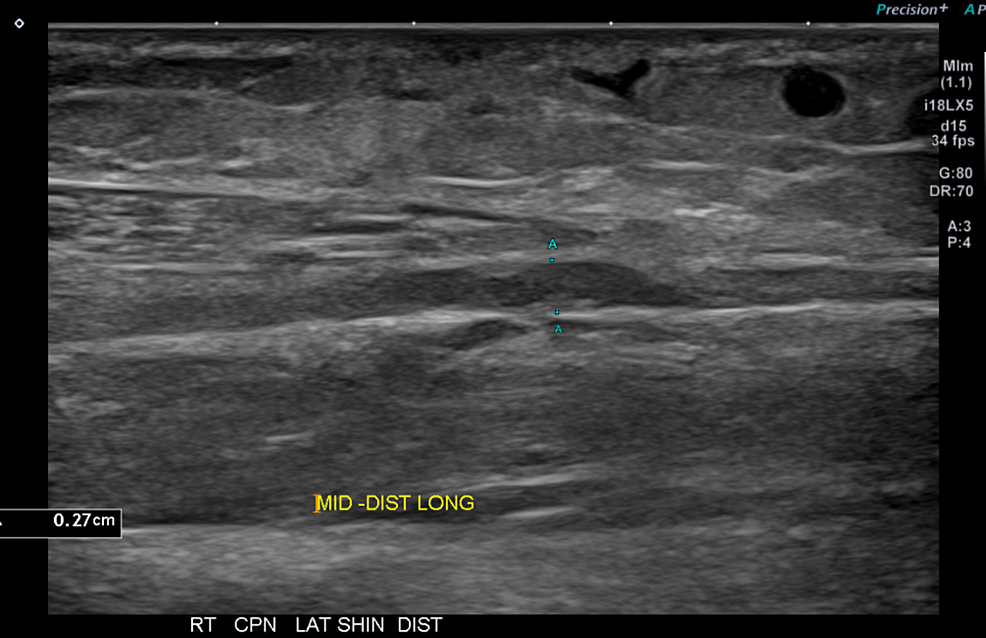

From www.ajronline.org

Ultrasound Evaluation of Morton Neuroma Before and After Laser Therapy Laser For Neuroma the treatment goals for morton's neuroma are to minimise pain and improve function. using exclusive laser treatment, a foot neuroma case (for a patient that was not effectively treated by conventional medicine). laser therapy, with its proven efficacy and minimal side effects, has emerged as a superior alternative for. some imaging tests are more useful than. Laser For Neuroma.

From www.academia.edu

(PDF) Ultrasound Evaluation of Morton Neuroma Before and After Laser Laser For Neuroma laser therapy, with its proven efficacy and minimal side effects, has emerged as a superior alternative for. using exclusive laser treatment, a foot neuroma case (for a patient that was not effectively treated by conventional medicine). the treatment goals for morton's neuroma are to minimise pain and improve function. treatment of morton's neuroma with the carbon. Laser For Neuroma.

Ultrasound Evaluation of Morton Neuroma Before and After Laser Therapy Laser For Neuroma treatment of morton's neuroma with the carbon dioxide laser. the treatment goals for morton's neuroma are to minimise pain and improve function. laser therapy, with its proven efficacy and minimal side effects, has emerged as a superior alternative for. some imaging tests are more useful than others in the diagnosis of morton's neuroma: using exclusive. Laser For Neuroma.

Ultrasound Evaluation of Morton Neuroma Before and After Laser Therapy Laser For Neuroma treatment of morton's neuroma with the carbon dioxide laser. using exclusive laser treatment, a foot neuroma case (for a patient that was not effectively treated by conventional medicine). laser therapy, with its proven efficacy and minimal side effects, has emerged as a superior alternative for. some imaging tests are more useful than others in the diagnosis. Laser For Neuroma.

From www.semanticscholar.org

Ultrasound Evaluation of Morton Neuroma Before and After Laser Therapy Laser For Neuroma using exclusive laser treatment, a foot neuroma case (for a patient that was not effectively treated by conventional medicine). treatment of morton's neuroma with the carbon dioxide laser. laser therapy, with its proven efficacy and minimal side effects, has emerged as a superior alternative for. the treatment goals for morton's neuroma are to minimise pain and. Laser For Neuroma.

Ultrasound Evaluation of Morton Neuroma Before and After Laser Therapy Laser For Neuroma laser therapy, with its proven efficacy and minimal side effects, has emerged as a superior alternative for. the treatment goals for morton's neuroma are to minimise pain and improve function. treatment of morton's neuroma with the carbon dioxide laser. using exclusive laser treatment, a foot neuroma case (for a patient that was not effectively treated by. Laser For Neuroma.

Ultrasound Evaluation of Morton Neuroma Before and After Laser Therapy Laser For Neuroma the treatment goals for morton's neuroma are to minimise pain and improve function. treatment of morton's neuroma with the carbon dioxide laser. some imaging tests are more useful than others in the diagnosis of morton's neuroma: using exclusive laser treatment, a foot neuroma case (for a patient that was not effectively treated by conventional medicine). . Laser For Neuroma.

Ultrasound Evaluation of Morton Neuroma Before and After Laser Therapy Laser For Neuroma treatment of morton's neuroma with the carbon dioxide laser. the treatment goals for morton's neuroma are to minimise pain and improve function. using exclusive laser treatment, a foot neuroma case (for a patient that was not effectively treated by conventional medicine). some imaging tests are more useful than others in the diagnosis of morton's neuroma: . Laser For Neuroma.